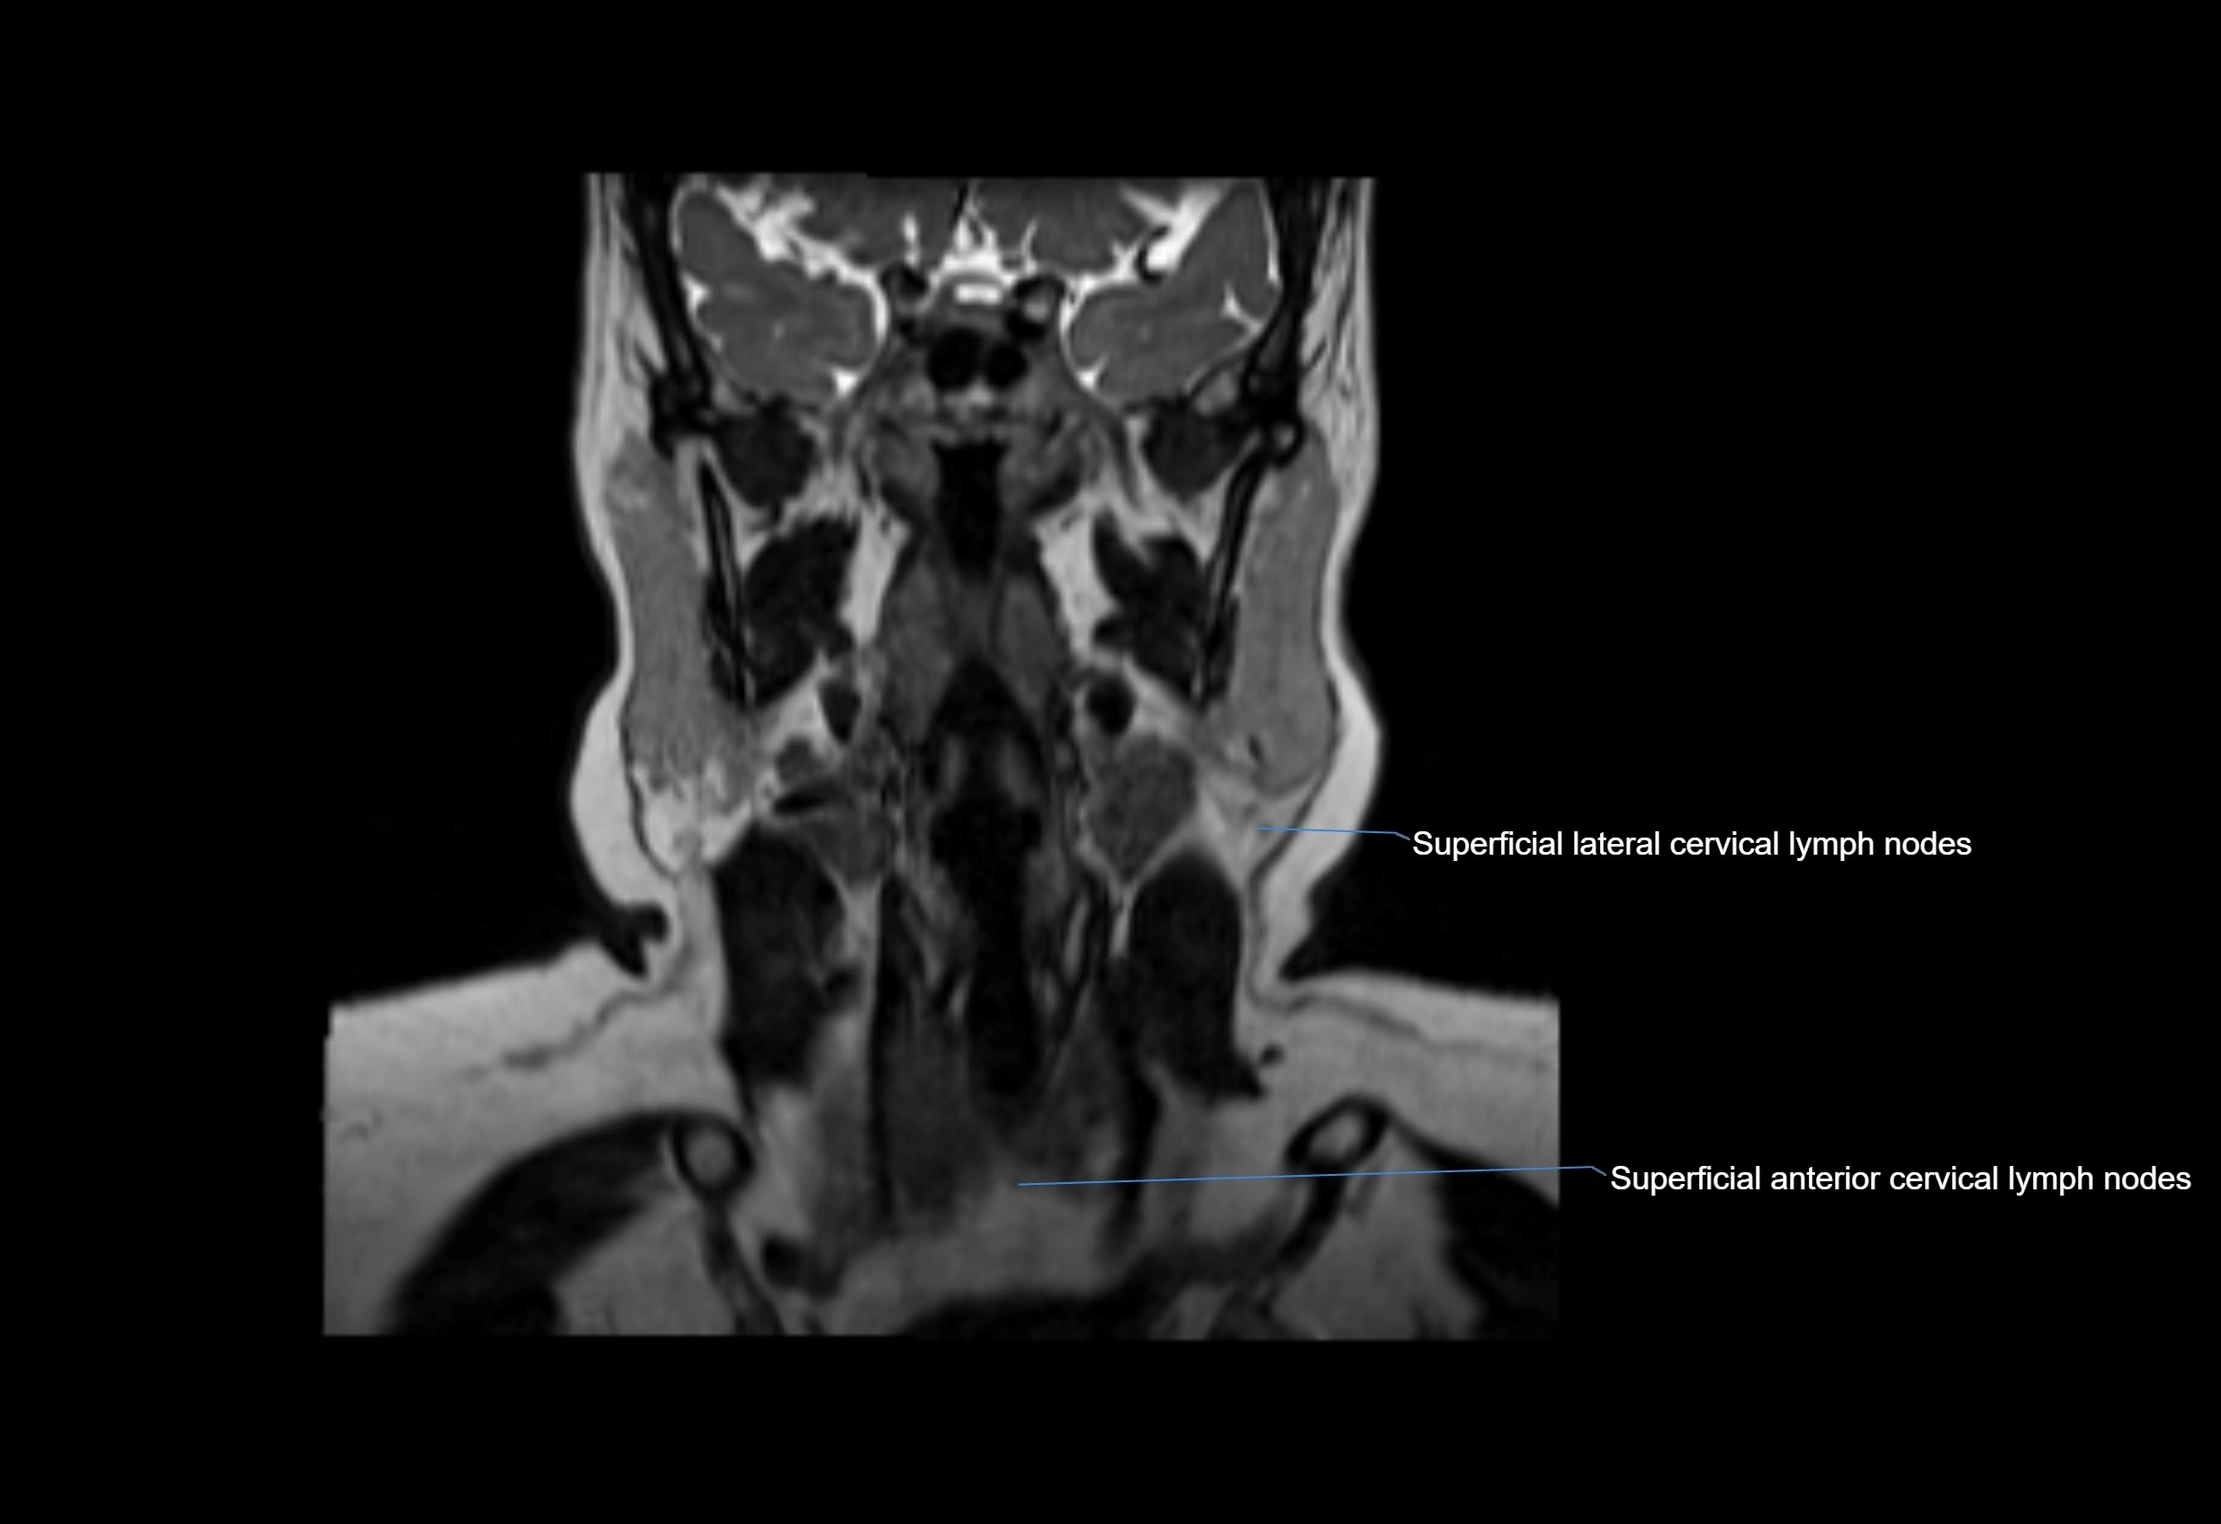

MRI images

image